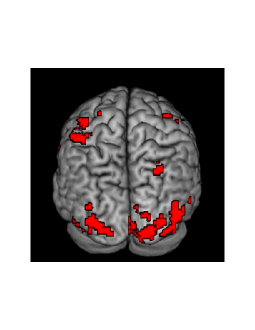

We next examine and make comparisons with respect to activations, more specifically, the effect of face by defining a contrast vector . The value of is set to be greater than the global mean (across voxels) of ([24]). The value of the probability threshold is set to be . We are then able to compute the PPM and they are depicted in Figure 9. A difference is observed where HMC tends to result in a smaller proportion of the brain indicated as ”active” compared with VB. The VB approximation thus results in a wider area of activation when compared with HMC. This result agrees with the simulation results in [5] where the authors suggest that VB seems to report more false positives. Again, this is a practically important difference that practitioners should be aware of.

The PPM’s obtained from the two approaches are generally similar, though with more voxels indicated as activated by VB in this particular case. In terms of timing, HMC takes 8.42 hours for 3000 iterations, VB takes 36 minutes, MUA takes 36 seconds with all computations performed on a standard iMac with with 3.2 GHz Intel Core i5.